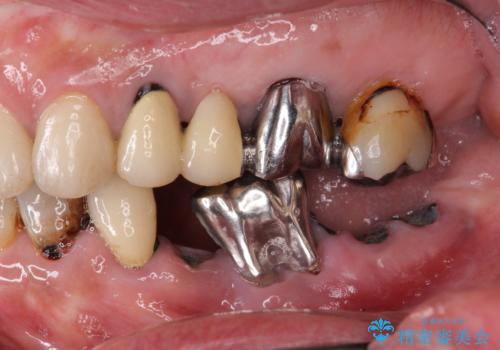

虫歯による歯の喪失 インプラントによる咬合機能回復

- 深い虫歯や歯の破折、多数の問題を口腔内に抱えて来院されました。

虫歯の徹底的な除去、安定した噛み合わせを達成するインプラント治療、深い虫歯、根管治療といった複数の治療項目を一つづつ積み重ね、長期的な予後を目指します。